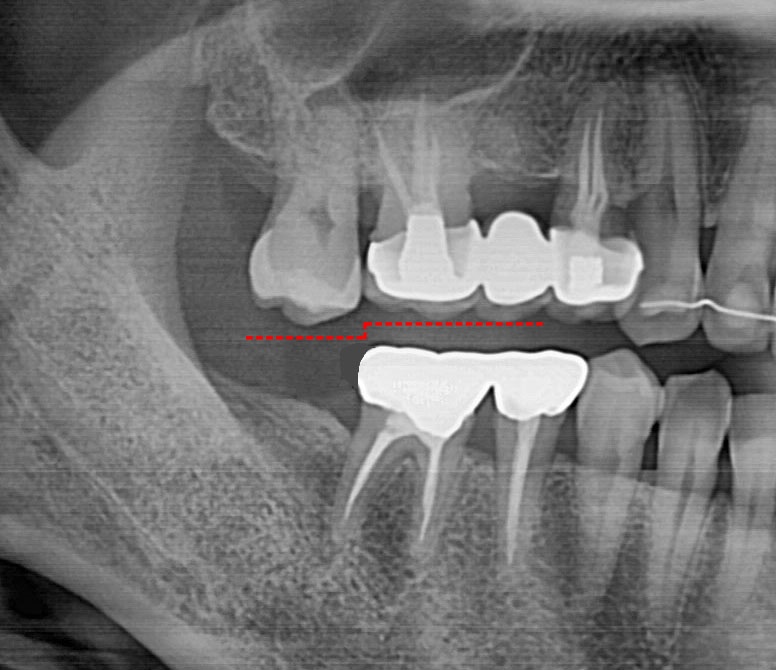

잇몸뼈의 비가역적 소실

사용하지 않는 뼈는 녹아 없어집니다. 방치 기간이 길수록 치조골 높이가 낮아져 임플란트 고정력을 확보하기 어려워지며, 고난도 뼈 이식 수술이 동반되어 치료 비용과 기간이 대폭 늘어납니다.